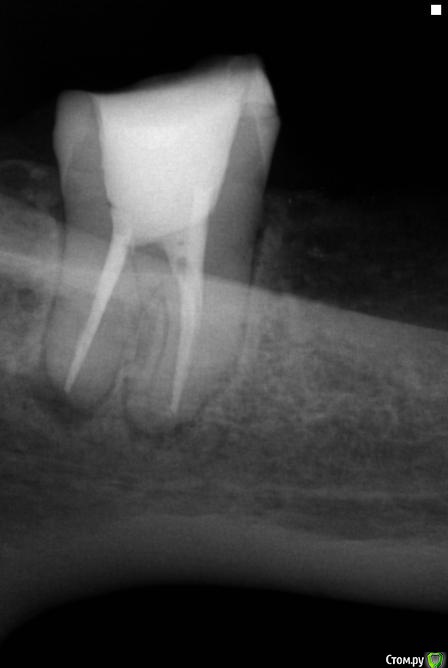

sabik Опубликовано 21 мая, 2019 Поделиться Опубликовано 21 мая, 2019 Здравствуйте, болит зуб снизу 7-ка справа (на снимке слева), болит уже второй год, причину боли не понимает никто, видимых изменений на корнях нет особых, в данный момент удалены нервы, каналов два, залили каласепт уже почти месяц как, а боль не утихает, она не острая, а тупая, ноющая, если сбоку надавить на зуб то чуть усиливается. Третий канал искали на КТ, его нет там, всего два канала, кист нет, небольшое расширение периодонтальной щели и все. Что может давать боль эту, к неврологу стоит идти? Не знаю уже что делать, ждать когда пройдет, сказали, но она не утихает, каласепт должен помочь уже или нет? Подскажите, может в вашей практике были случаи такие? Удалять не хочется этот зуб без видимой причины, может ли быть это не связано с зубом, а с невритом нерва нижнечелюстного какого-нибудь? Есть ли смысл лазером прогревать? Очень жду ваших мнений. Ссылка на комментарий

sabik Опубликовано 28 сентября, 2019 Автор Поделиться Опубликовано 28 сентября, 2019 Прошло почти 3 мес, зуб болит по прежнему тупой ноющей болью, воспаление на корнях говорят не проходят, запломбировали каналы сейчас эндометазоном и временной пломбой закрыли, если не пройдет, сказали придется зуб удалять . После пломбировки каналов этой пастой, зуб все равно ноет, во рту привкус лекарства, горечь сильная и тошнота, подскажите пожалуйста это нормальная реакция, пройдет это, не вредно ли для организма? Я так понимаю, временная пломба пропускает препарат, надо ли просить врача ставить постоянную? Посмотрите снимок после пломбировки, что с этим зубом, почему болит он и надо ли удалять его? Ссылка на комментарий

DmitrySH Опубликовано 29 сентября, 2019 Поделиться Опубликовано 29 сентября, 2019 По снимку каналы запломбированы нормально, но возможно в зубе есть еще ненайденные каналы. Сделайте КТ данного зуба 1 Ссылка на комментарий